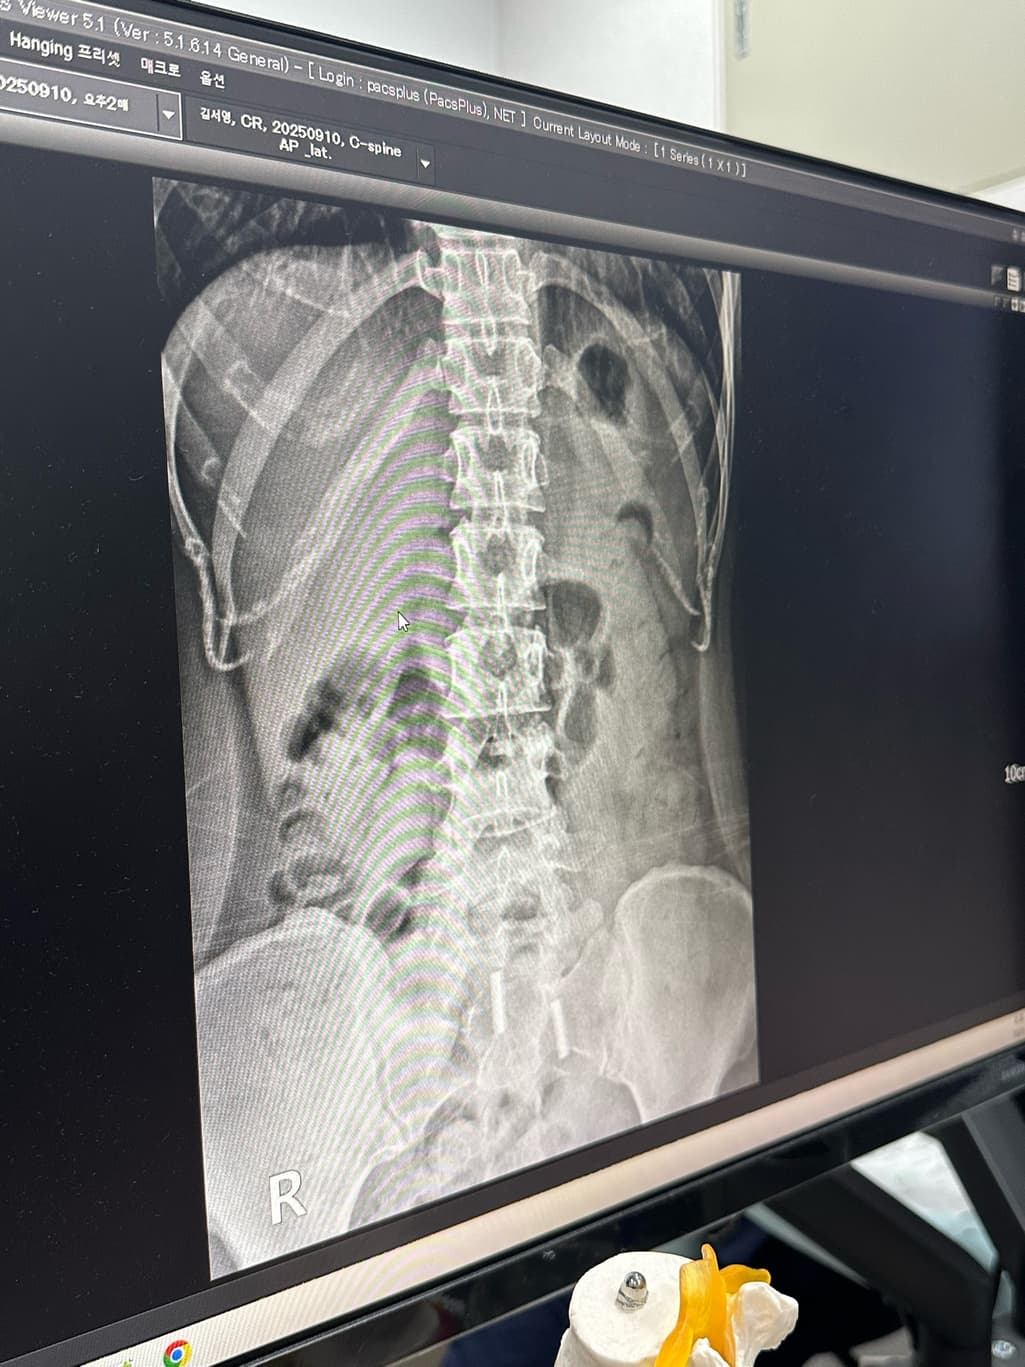

집에서 운동하면 휜 허리나 거북목이 다시 돌아올수 있을까요?? 집에서 허리운동해도될까요? 그리고 제가 허리디스크인지도 궁금합니다 까먹고 못물어봤어요 디스크사이에 공간이 있어야하는데 줄어들어잇다 하더라고요

X-ray상으로 디스크를 정확하게 알 수는 없으며 척추체 사이가 간격이 좁아져 있다면 디스크 이상을 의심해볼 수 있습니다.

X-ray상 골반틀어짐, 척추측만증 등 전체적으로 신체 균형이 틀어져 있는 것으로 보이며 잘 못된 운동은 증상을 더 악화시킬 수 있기때문에 정형외과에서 진료받으시고 체형교정을 위한 도수치료를 받으시는 것이 도움이 되실 것입니다.

다만 디스크 질환의 경우에는 단순히 공간이 좁아진 것 뿐만 아니라 이로 인해 발생하는 신경압박으로 인해 나타나는 증상이 동반되기 때문에, 단순히 공간이 줄어든 것이 디스크가 있다고 보기는 어렵습니다.

마지막으로 엑스레이상으론 현재 디스크를 판단하기 어렵지만 소견 중 디스크 공간이 줄었다는것은 디스크의 가능성이 높으니 주의하시는게 좋습니다.